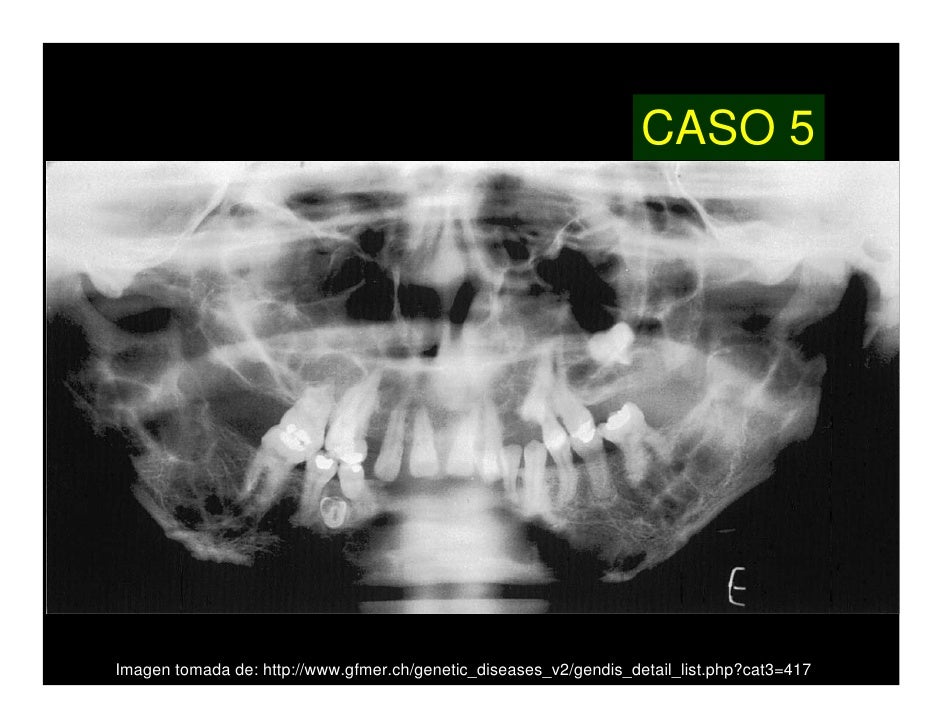

El trastorno origina un aspecto característico de la cara que recuerda a las representaciones de querubines, de donde toma su nombre. Existe aumento de tamaño bilateral de la mandíbula asociado a tumores quísticos no malignos. Además de las deformidades faciales que tienen importancia desde el punto de vista estético y psicológico, pueden existir complicaciones, entre ellas pérdida de visión por neuropatía óptica, obstrucción de vías aéreas superiores, apnea del sueño, trastornos del lenguaje y dificultad para la masticación por alteraciones en la aparición y desarrollo de las piezas dentales.[1] [2][3]